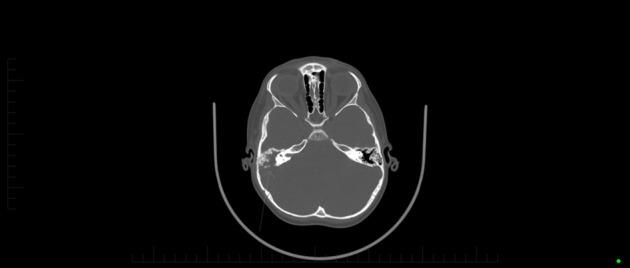

We report the case of an immunocompetent 5-year-old boy with recurrent otitis media who re-presented to the emergency department with a 3-week history of otorrhoea, progressive anorexia, vomiting and lethargy. He was admitted with a working diagnosis of otitis media and dehydration, and was treated with intravenous fluids and oral co-trimoxazole. He subsequently developed abnormal posturing with a reduced Glasgow coma score and seizures. Urgent computed tomography revealed a cerebellar abscess with obstructive hydrocephalus for which he underwent urgent neurosurgical intervention. Tissue and aspirate cultures revealed a polymicrobial infection with . The patient has since undergone long-term antibiotic treatment and has made a good recovery.

我们报告一例免疫功能正常的5岁男孩,有复发性中耳炎病史,因耳漏、进行性厌食、呕吐和嗜睡3周再次就诊于急诊科。他因中耳炎和脱水的初步诊断入院,接受了静脉补液和口服复方新诺明治疗。随后他出现异常姿势,格拉斯哥昏迷评分降低并伴有癫痫发作。紧急计算机断层扫描显示小脑脓肿伴梗阻性脑积水,为此他接受了紧急神经外科干预。组织和抽吸物培养显示为[此处原文缺失相关内容]的混合感染。此后,该患者接受了长期抗生素治疗,恢复良好。